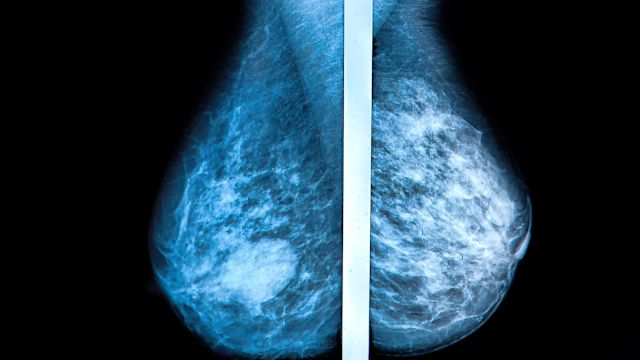

Mammograms are the best tests doctors have to find breast cancer. These X-ray pictures can help detect changes in breast tissue early on—up to three years before they can be felt.

Mammogram results are usually received within a few weeks, although the timing may vary from one facility to the next. One important finding on mammography reports is breast density—the ratio of fatty tissue to fibrous or glandular tissue. Those with mostly fibrous or glandular tissue (about 50 percent of women age 40 and older) have dense breasts, increasing their risk for developing breast cancer.

Because breast tissue looks white, as do masses and tumors, it’s possible that dense breast tissue can prevent radiologists from detecting cancer during mammograms. As a result, your mammogram may not be as accurate as it would be if you had more fatty tissue.